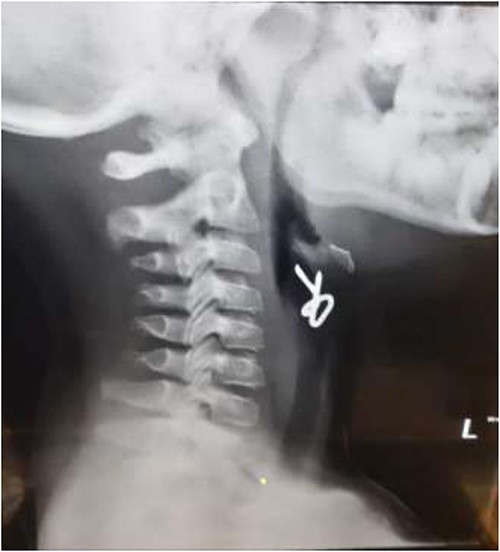

The final case is of a 75-year-old female who presented to hospital after inhalation of her dentures (Figs 6 and 7). After discussion with the anaesthetic team, apnoeic oxygenation was once again utilized in order to remove the foreign body without risk of dislodgement and to decrease the risk of a potential surgical airway (Fig. 8).

Lateral neck X-ray showing radio-opaque object in the upper airway.